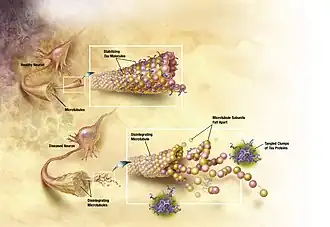

Age-related neuropathologies such as Alzheimer's disease, Parkinson's disease, diabetes, hypertension and arteriosclerosis make it difficult to distinguish the normal patterns of aging.[18][19] One of the important differences between normal aging and pathological aging is the location of neurofibrillary tangles. Neurofibrillary tangles are composed of paired helical filaments (PHF).[20] In normal, non-demented aging, the number of tangles in each affected cell body is relatively low[20] and restricted to the olfactory nucleus, parahippocampal gyrus, amygdala and entorhinal cortex.[21] As the non-demented individual ages, there is a general increase in the density of tangles, but no significant difference in where tangles are found.[21]

The other main neurodegenerative contributor commonly found in the brain of patients with AD is amyloid plaques. However, unlike tangles, plaques have not been found to be a consistent feature of normal aging.[21]